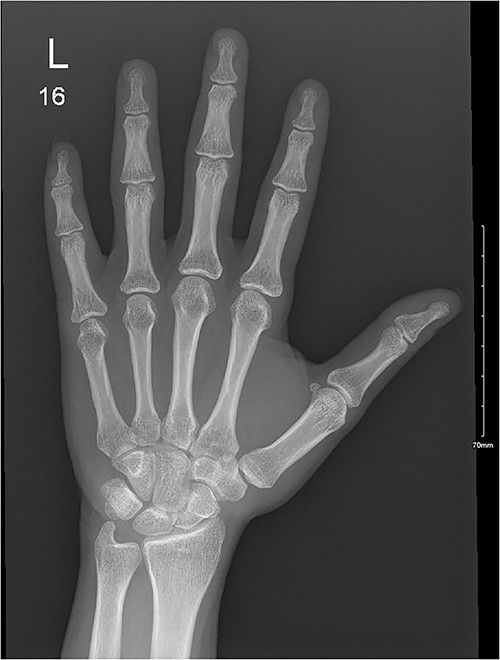

A 28-year-old female came to the emergency room (ER) following an MVA with airbag-deployment 5 days before presentation. Examination revealed tenderness at the base of the proximal fifth finger. The ROM of the affected digit was limited, but the neurovasculature as well as flexor digitorum profundus and flexor digitorum superficialis function were intact. X-ray of the hand showed a minimally displaced fracture at the base of the proximal fifth phalanx extending into the articular surface (Fig. 5). The decision was made to manage the patient conservatively by applying an ulnar gutter splint, which was then changed to a volar splint when the patient was followed-up in the clinic a week later. When the patient was last seen, the patient had limited ROM, and the tenderness had resolved. Imaging showed evidence of ongoing healing (Fig. 6).

A minimally displaced fracture at the base of proximal fifth phalanx extending into the articular surface.